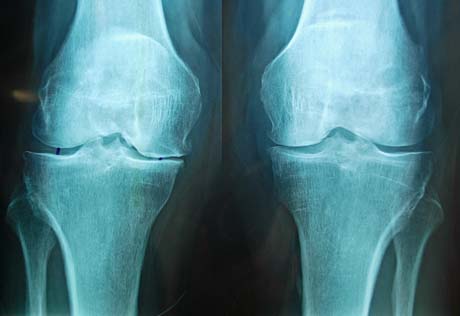

Pre-op X-rays. Severe degenerative osteoarthritis of the knees with varus deformity

Pre-op X-ray. Knees osteoarthritis

Pre-op X-ray. Osteoarthritis of the right knee

Pre-op X-ray. Knee osteoarthritis bilaterally – especially left

Pre-op X-ray. Severe knee osteoarthritis bilaterally

Pre-op X-ray. Valgus deformity of the knees